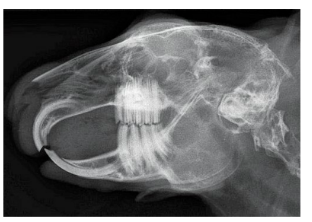

Most common dental pathology of rabbits

A

Malocclusion

how many millimeters do rabbit teeth grow in a week

2-3 mm